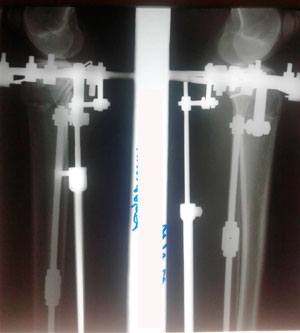

Исходник - 33 года.

Дата операции - 27.12.2019г.